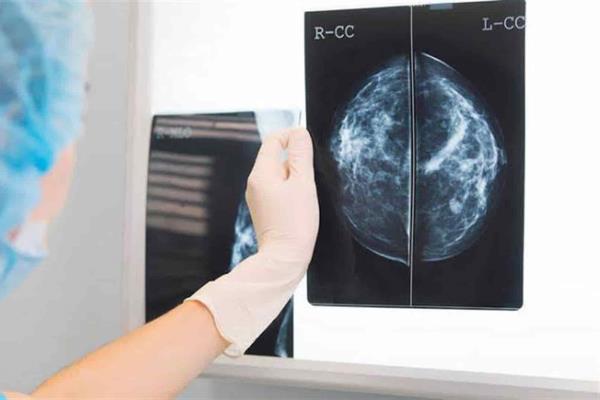

Encuentran proteína que suprime metástasis de cáncer de mama

Ciudad de México.- Científicos de la Universidad de Baylor, en Estados Unidos, encontraron una proteína, producida de forma natural por el cuerpo, que puede suprimir la metástasis del cáncer de mama, según un estudio publicado en la revista Nature Communications.